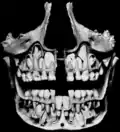

![]() Dientes permanentes de la mitad derecha del arco dentario inferior visto desde arriba. | ||

Imágenes

-

Boca (cavidad oral). -

Maxilar izquierdo. Superficie externa. -

Base del cráneo. Superficie interna. -

Diente permanente sin erupcionar bajo la línea de la dentición decidua. -

Caninos, muy desarrollados, en un gato doméstico.